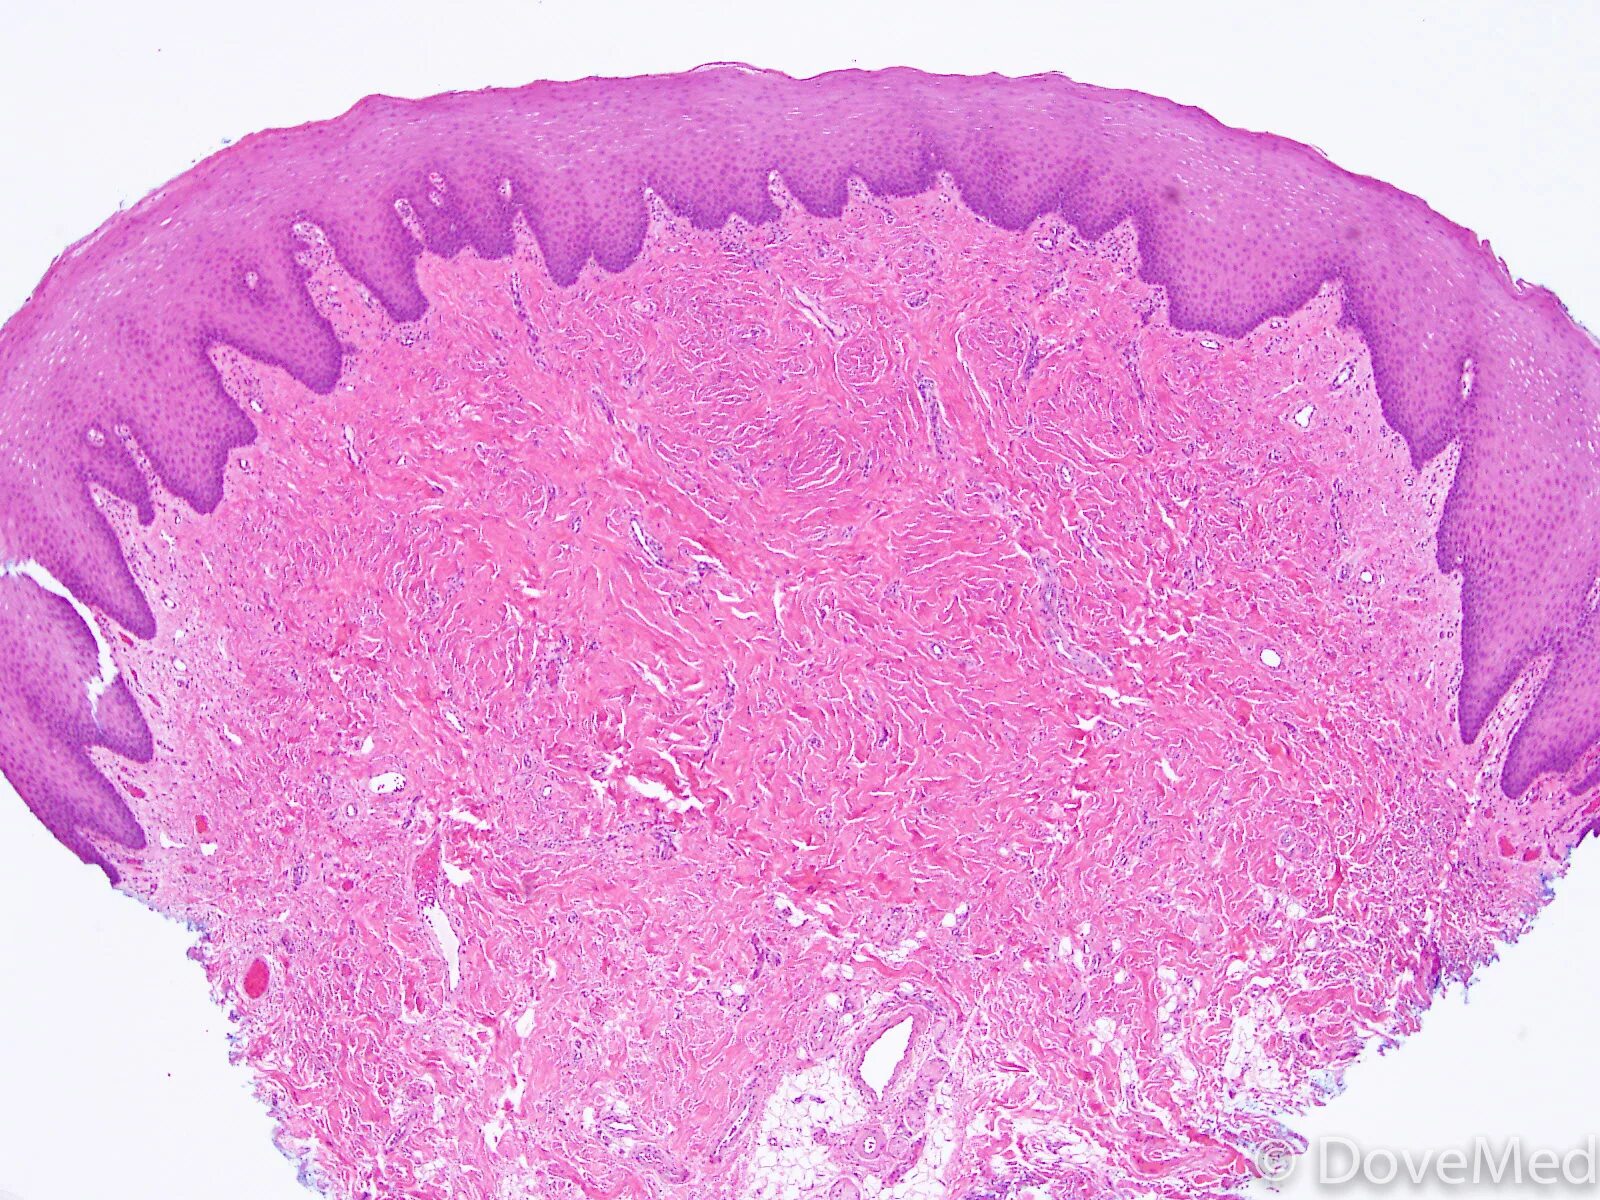

Фиброматоз мягких